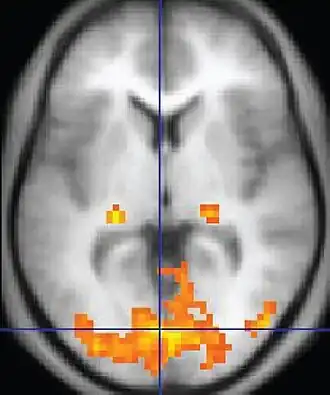

| Functional MRI (fMRI) | Blood-oxygen-level dependent imaging | BOLD | Changes in oxygen saturation-dependent magnetism of hemoglobin reflects tissue activity.[92] | Localizing brain activity from performing an assigned task (e.g. talking, moving fingers) before surgery, also used in research of cognition.[93] |

|